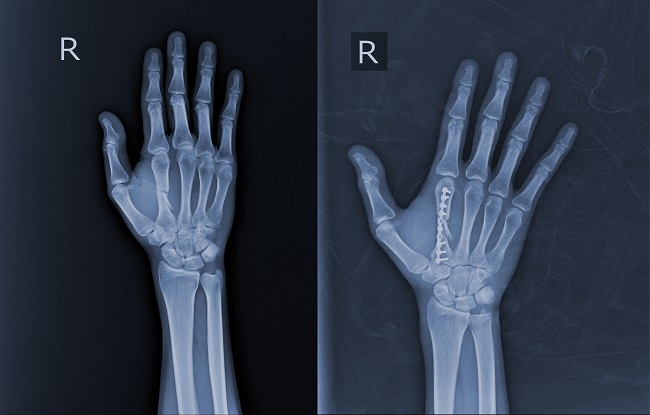

Pin vs Plate Fixation for Metacarpal Fractures: A Meta-Analysis

Tinjauan ini membandingkan dua teknik fiksasi pada fraktur metakarpal, yaitu reduksi tertutup dengan pin dan reduksi terbuka dengan ORIF menggunakan plate. Tujuan dari tinjauan ini adalah melakukan pencarian literatur sistematik dan meta analisis yang membandingkan kedua teknik terhadap luaran disabilitas ekstremitas atas, range of motion, dan kekuatan genggaman sebagai pembaruan dari meta analisis yang sudah ada.

Luaran sekunder pada studi ini, antara lain skor VAS, komplikasi, waktu union, dan residual angulation juga menunjukkan tidak adanya perbedaan signifikan antara kedua modalitas intervensi. Namun, pada salah satu luaran sekunder, limb shortening melalui pencitraan radiologi, ditemukan bahwa subjek yang menerima fiksasi dengan pin mengalami limb shortening yang lebih banyak bila dibandingkan dengan subjek yang menerima fiksasi plate.